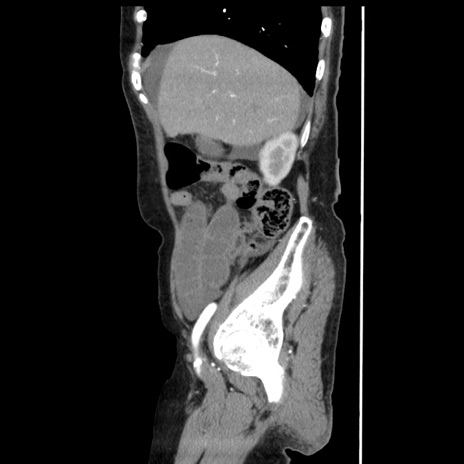

症例1(矢状断像)

【症例】80歳代女性

【主訴】腹痛

【現病歴】8時間前から腹痛あり来院。

【既往歴】糖尿病、脂質異常症、子宮体癌にて子宮全摘術

【身体所見】意識清明・会話良好だが腹痛で苦悶様、全腹部にわたって反跳痛と圧痛あり

【データ】WBC 13600、CRP 0.14、LDH 224、CK 90